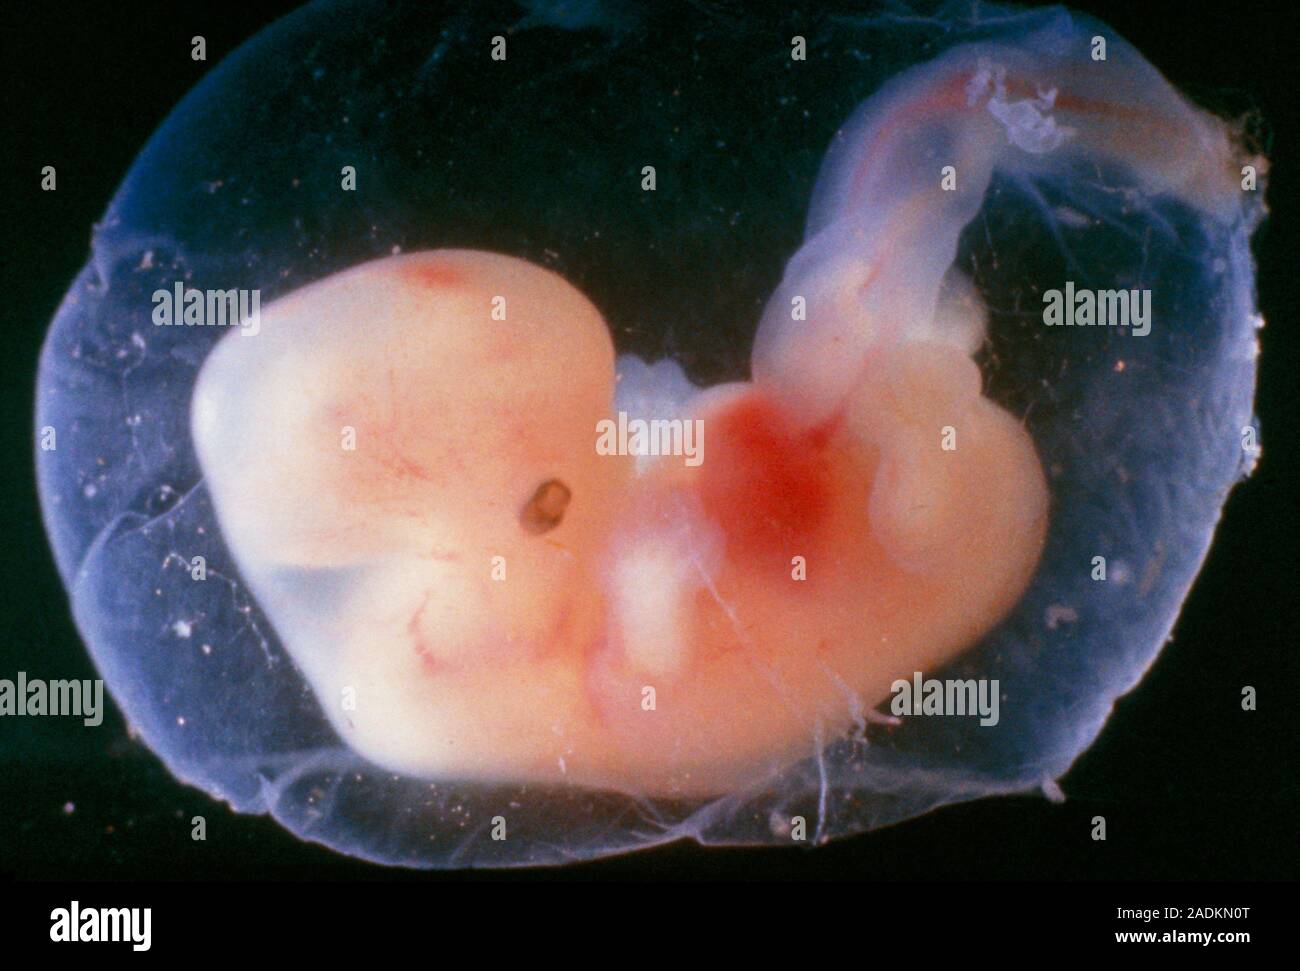

Развитие эмбриона: Что происходит на 3 неделе беременности